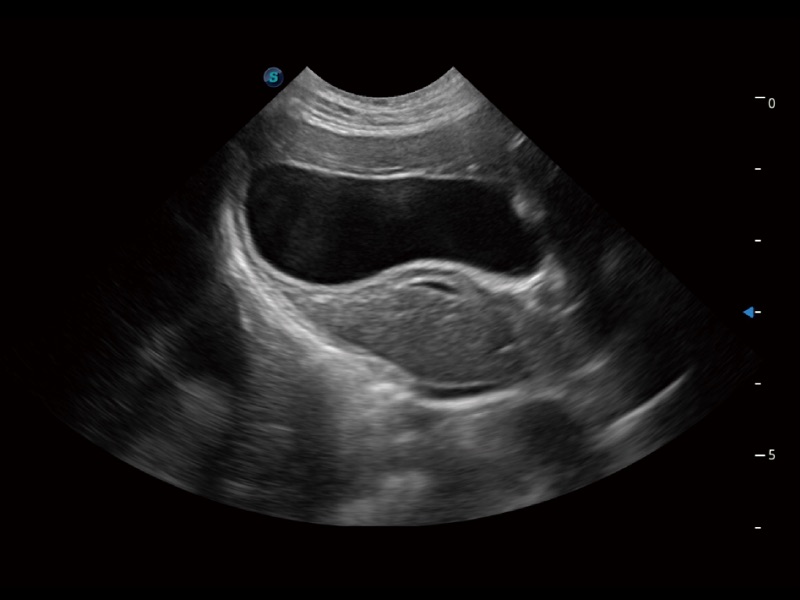

通過360度任意調(diào)節(jié)3條M型取樣線,在同一心動(dòng)周期上觀察心臟不同位置的運(yùn)動(dòng)曲線,得到準(zhǔn)確的心功能測(cè)量數(shù)據(jù),有效評(píng)估心肌運(yùn)動(dòng)及左心室功能。